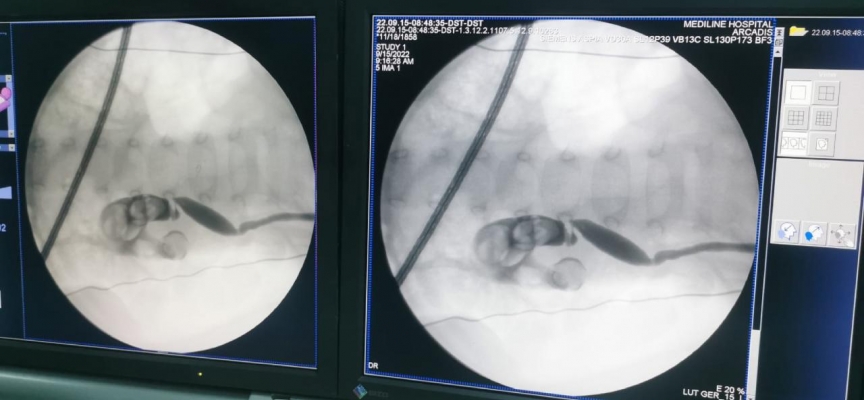

Tetkiklerde bebeğin sol böbreğini kaplayan 5 santimetre büyüklüğünde taş olduğu tespit edildi.

Üroloji Uzmanı Serhat Yentür tarafından gerçekleştirilen kapalı ameliyatla bebeğin böbreğindeki taş kırılarak çıkarıldı.

Yentür, gazetecilere yaptığı açıklamada, 13 aylık bebeğin böbreğinde bu kadar büyük taşı ilk defa gördüğünü söyledi.

Kapalı yöntemle böbrekteki taşı kırarak büyük bölümünü çıkardıklarını aktaran Yentür, "Tamamen temizlemek imkansız çünkü böbreğin içi oda oda yani bir boşluk şeklinde değil. Çocuğa zarar veren yüzde 99'a yakını temizlendi. Kalan taşlar da ekstra daha basit tedavi yöntemleriyle temizlenecek" diye konuştu.